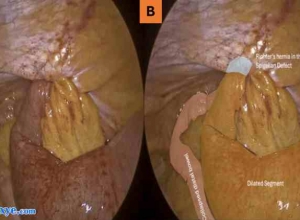

倒钩缝合术在腹腔镜胆囊切除术中胆管损伤修复中的应用——附2例报告Effectiveness of a barbed suture in the repair of bile duct injury during laparoscopic cholecystectomy- Report of two casesAbstract摘要IN ...